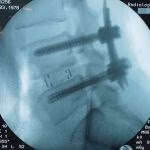

- Artrodese lombar

- ALIF, OLIF, TLIF